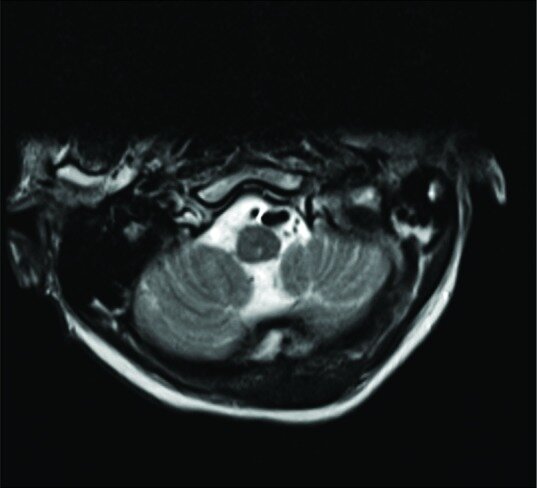

Case description: A 64-year-old neurologically intact patient with a type II odontoid fracture secondary to trauma underwent anterior odontoid screw fixation without any intraoperative complications. He tolerated the procedure well, and postoperative imaging demonstrated near anatomic correction of the fracture with satisfactory placement of the lag screw. Unfortunately, the patient was subsequently lost to follow up and he presented 7 months later for a routine outpatient computed tomography (CT) of the cervical spine, which demonstrated upward migration of the screw into the intracranial cavity abutting the medulla, with CT angiography of the neck also confirming the screw lying between the two vertebral arteries. Magnetic resonance imaging of the cervical spine also demonstrated the odontoid screw lying within close proximity to the ventral cervicomedullary junction, marginating the left vertebral artery. Subsequently, the patient was managed with removal of the odontoid screw and posterior cervical arthrodesis and instrumented fusion.